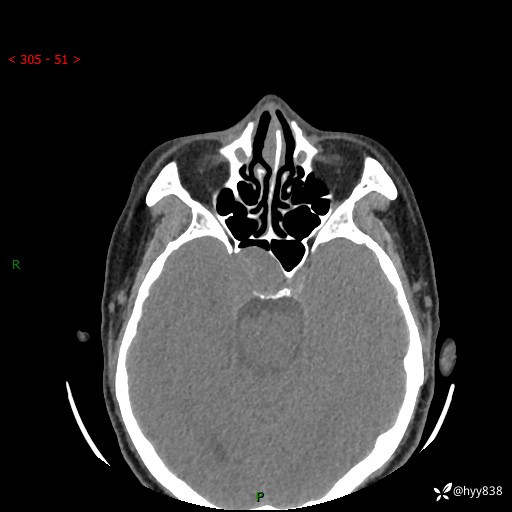

蝶鞍CT平扫